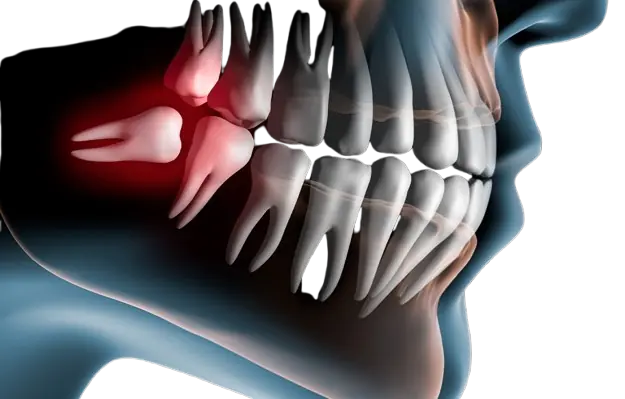

Impacted Wisdom Teeth

Causing persistent pain, swelling and discomfort that affects your daily life and oral health.

- Pain and swelling in back of mouth

- Difficulty opening mouth fully

- Risk of cyst formation

- Can damage adjacent teeth